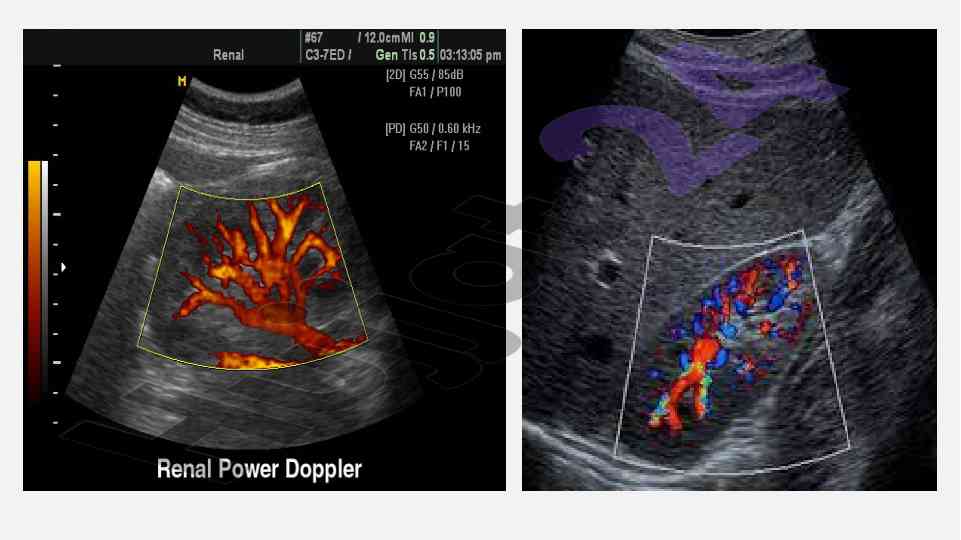

Ushbu maqola buyrak va siydik yo'llari nurli tekshirish usullarini, jumladan, sonografiya va ekskretor urografiyani, ularning afzalliklari va kamchiliklarini o'rganadi.